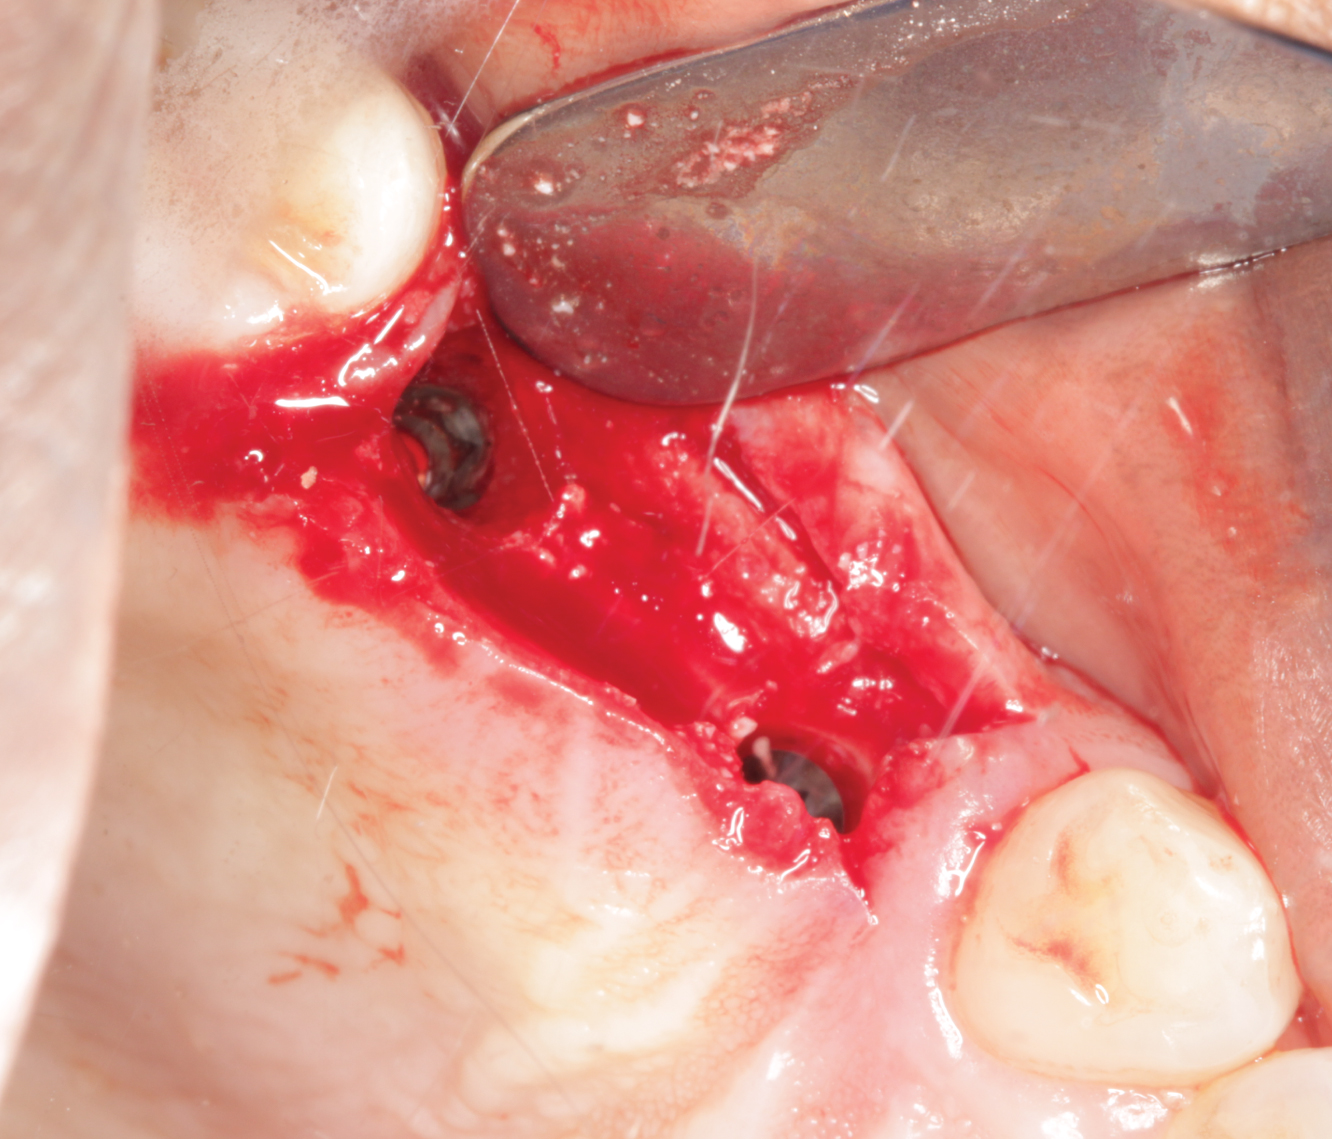

Director’s Clinical Cases

Director’s Clinical Cases